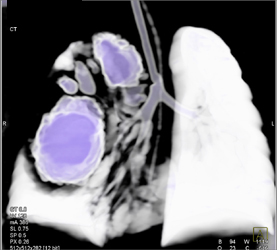

Pulmonary Embolism